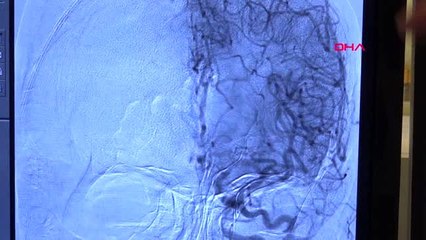

Hastadan görüntübr -Hasta kontrolü yapılırken görüntübr -Hastanın değerlerine bakılmasından görüntübr -Doktorun tabelasından görüntübr -Doktor Hakkı Şimşek röportajıbr -Aysel Şahin röportajıbr -detay görüntülerbrbr( DİYARBAKIR -ÖZEL) DİYARBAKIR br br – Malatya’da yaşayan 56 yaşındaki Yeter Levent’e nadir görülen kalp kası hastalığı tanısı konuldu. Malatya’da tedaviden sonuç alamayan Levent, Dicle Üniversitesi Kalp Hastanesinde geçirdiği başarılı operasyonla sağlığına kavuştu. Doğuştan kalp kası hastalığı bulunan Yeter Levent, Malatya’da nefes darlığı, çarpıntı şikayetleri ile hastaneye başvurdu. Yeter için burada yapılan tetkikler ve müdahaleler sonuç veremeyince çocukları hastalıkla ilgilenen doktor bulmak için internetten araştırma yaptı. Çocuklarının yapmış olduğu araştırma sonucu Dicle Üniversitesi Kalp Hastanesinde görevli Kardiyolog Doç. Dr. Hakkı Şimşek’e ulaşıldı. Tedavi için Diyarbakır’a gelen Yeter Levent, burada geçirdiği kapalı operasyonla sağlığına kavuştu. Kardiyolog Doç. Dr. Hakkı Şimşek, hastanın nefes darlığı ve çarpıntı şikayetlerinin ön planda olduğunu söyledi.brbr Doç. Dr. Şimşek, “Oğlu internetten araştırmış bizim ismimizi bulmuş, buradan bir hoca aracılığıyla irtibata geçtiler. Doğuştan kalp kası kalınlaşmasına bağlı kalbin vücuda kanı pompalamada zorluk çekmesi ve bunun sonucunda halsizlik, yorgunluk, çarpıntı, çok ileri evrelerde bayılma şikayetleri oluşan bir hastalık. Doğuştan olan bir hastalık ve bizde gerçekten yaptığımız tetikler sonucu hastanın teşhisini doğru konulduğunu, tedavi için de iki farklı tedavi yönteminde yakınları cerrahi tedavinin riskini üstlenmek istememişler. Kapalı yöntem dediğimiz anjiyografi grafik yöntemle tedavi yöntemi arayışı içine girmişler. Bize geldiler, biz de baktık değerlendirdik gerçekten bu tedavi yöntemini uygulayabileceğimiz bir hasta olduğuna karar verince hastamızın önce anjiyosunu yaptık. Damar yatağını ortaya koyduk, daha sonra müdahale etmek üzere çağırdık. Hipertrofik kardiyomyopati hastalığı. Septal alkol ablasyonu denen anjiografik yöntemle ameliyata gerek kalmadan yarım saatlik müdahale ile kalp kasındaki kalınlığa müdahale edildi. Hasta 2 gün sonra taburcu edildi” dedi.br “Müdahale deneyimli hekimler tarafından yapılmalı” Gerçek değerini bir ay sonra değerlendirdiklerinde göreceklerini ama erken dönemde bu kadar büyük bir başarı sağlanmasının kendileri için de tatmin edici bir işlem olduğunu kaydeden Doç. Dr. Hakkı Şimşek, sözlerine şöyle devam etti: “Hastamızın şikayetlerinde rahatlama olduğunu hastanın demin size de ifade ettiği gibi rahatladığını söyledi.brbr Biz tabii bunu 1 ay içinde göreceğiz. Hastanın yaşam kalitesi artışını bir ay içindeki gözlemimizde daha da pekiştirmiş olacağız. Bu çok riskli bir müdahale, yani burada kanın duvarlarının yırtılma riski yine pile bağlantılı hale gelme riski çok önemli. Bizi en çok korkutan iki tane komplikasyonumuz bir kalp duvarının yırtılması, iki orada yaptığımız müdahale sonucu hastanın ömür boyu pile bağlı hale gelme riski vardı. Doğuştan görülen kalp kası hastalığı oldukça nadir bir hastalık ve müdahalesinde ileri derecede deneyim gerektiren hekimler tarafından yapılması gerekir. Bu şeyin cerrahisi de aynı şekilde deneyimli cerrahlar tarafından yapılması gereken bir hastalık.” Hastanın kızı Aysel Şahin ise, annesinin merdiven çıkmakta zorlandığını söyledi.brbr Şahin, “Merdivende çıkarken, bir iş yaptığında fazlasıyla yoruluyordu. Biz annemi Malatya’da doktora götürdük ve Malatya'da annemin kalp kası kalınlaşması olduğunu söylediler. Biz bu noktada araştırma yaptık. Hakkı Şimşek hocanın bu alanda farklı bir uygulama yaptığını öğrendik. Hocamla irtibata geçtik ve hocam sağ olsun bizimle ilgilendiler, güzel bir operasyon geçirdiler. İnşallah Allah bundan sonraki süreçte de sıkıntısı olmayacağını düşünüyorum ve şimdiden rahatladığını söylüyor annem” diye konuştu.